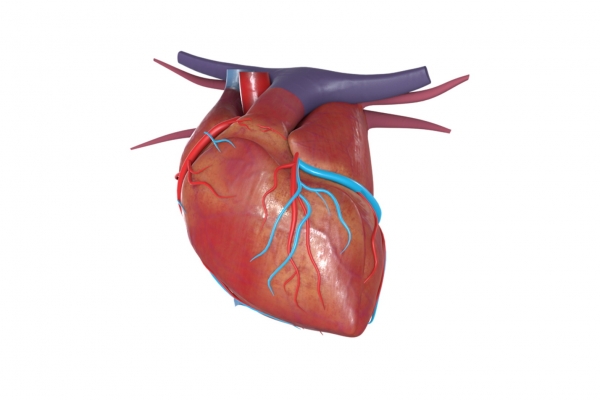

2、健康心脏。卵磷脂可以调节人体中胆固醇的含量,降低胆固醇、高血脂、冠状粥脉硬化性心脏病的发病率,让心脏更健康。

3、保护血管。卵磷脂可以乳化和分解油脂,还可以促进血液循环,清除血液中的过氧化物和多余胆固醇、脂肪,减少脂肪在血管壁的停留,防止血管内膜损伤,让血管更加健康干净,从而预防和治疗高血脂、高胆固醇以及动脉硬化。